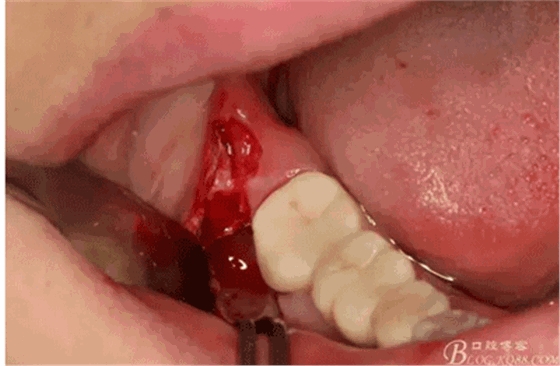

圖8.在頰側(cè)做角形切口

圖10.去骨暴露出48牙冠

圖12.然后再把牙冠近遠中向縱斷。

圖14.挺松牙根部分

圖15。為了減少去骨,又把牙根橫分成兩塊取出來,這是拔完牙后的牙槽窩情況,我提倡小切口、翻小瓣、少去骨、多分牙原則。目的是為了減輕術(shù)后反應(yīng)。

圖18.大卸八塊的牙齒,之所以分這么多塊,就是為了取這些牙體組織的時候不會碰到前面的47全瓷冠。